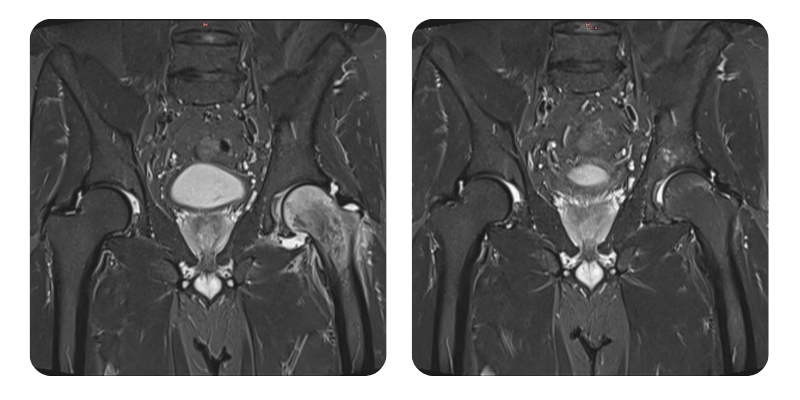

Vorher

Nachher

J.A.V., 43 Jahre – Ödem des linken Femurkopfes

Diagnose: Ödem des linken Femurkopfes.

Therapeutische Maßnahmen: 20 Sitzungen hyperbarer Sauerstofftherapie.

Eine Reduktion des Ödems um über 90 % wurde festgestellt; klinisch korrelierend wird der Patient als geheilt betrachtet.